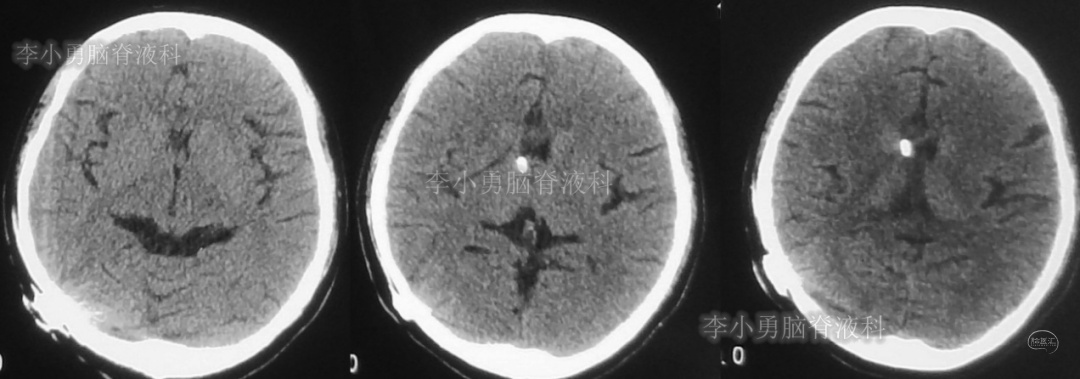

患者于2018年1月29日,突发头痛、头晕、恶心、呕吐,并高热40度。在当地医院门诊输入4天抗生素后发热缓解,但出现了双眼不能上视(眼球不能向上看)。5天后即2018年2月3日,在当地的第1家医院:浙江省海宁市某医院行头颅CT(图-1)发现脑室扩张,当地医院诊断为“梗阻性脑积水”。

图-1:2018年2月3日头颅CT